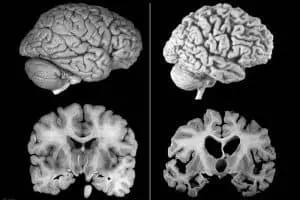

Все още няма ясна идея какво точно причинява болестта, но е ясно, че щетите върху мозъка са предизвикани от т.нар амилоидни плаки, съставени от грешно сгънати протеини. Те се разполагат около коровите клетки, сплетенията, които са разположени в мозъчните клетки или в невроните. Това води до загуба на връзките между клетките и до загуба на неврони. Заболяването се развива бавно, но упорито, и с времето мозъкът се влошава сериозно – боледуващите губят не само спомените си, но забравят как да се хранят, как да се движат, как да преглъщат, как да дишат. Повечето живеят между 8 и 12 години след диагнозата.

Новият медикамент изчиства амилоидните плаки почти напълно при високите дози след година приемане. При групите с плацебо няма разлика, а тези с по-малки дози са получили съответно по-малко изчистване.